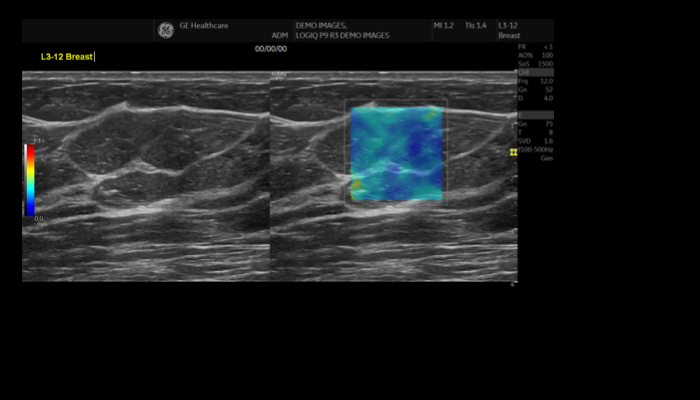

エコー検査装置 エコー検査装置GE社製エコー検査装置 心臓エコー 心臓心臓の動きや心臓弁膜症を調べます。 乳腺エコー 乳腺高濃度乳房の方はマンモグラフィでは病気が見つけにくいことがあります。エコーと併せて評価をお勧めします。 腹部エコー 腹部肝臓、胆嚢、膵臓、腎臓、脾臓など腹部の重要臓器を調べます。 頸部エコー 血管頸動脈の狭窄や下肢の静脈の流れを見ます。脳梗塞や深部静脈血栓症のリスクを調べます。 甲状腺エコー 甲状腺甲状腺腫瘍やバセドウ病など甲状腺疾患を調べます。